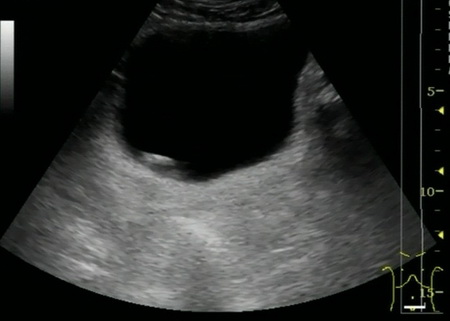

Из анамнеза: с 2013 года периодически отмечает примесь крови в моче с бесформенными сгустками. По месту жительства, при УЗИ выявлено образование мочевого пузыря в области правого устья размером 30*9мм. Выполнена компьютерная томография органов брюшной полости и малого таза, по данным которой образование подтвердилось. Пациент был направлен в клинику урологии Первого МГМУ им. И.М. Сеченова. Госпитализирован для дообследования и определения дальнейшей тактики лечения.

Рис. №1. УЗИ мочевого пузыря.